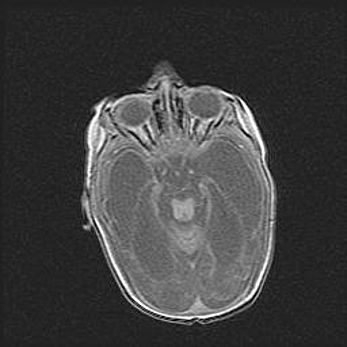

Наружная гидроцефалия с возможной атрофией височных областей.

Возраст: 28 дней

Вес: 3670 г

Пол: мужской

Окружность головы: 38 см

Срок гестации: 40 недель

Гидроцефалия головного мозга у новорожденных – это заболевание, которое характеризуется скоплением избыточного количества спинномозговой жидкости в желудочковой системе головного мозга в результате затруднения её перемещения от места выработки к месту поглощения в кровеносную систему или вследствие нарушения абсорбции. При открытой наружной форме гидроцефалии у новорожденных расширяются и переполняются субарахноидные пространства.

При нормотензивных  формах,  которые,  как  правило,  являются  следствием  перенесенных ишемических  повреждений  паренхимы  мозга,  возможно  сочетание микроцефалии  с нормотензивной гидроцефалией. В основе данных изменений лежит атрофия больших полушарий с преимущественной  локализацией  в  лобно-височных  областях.